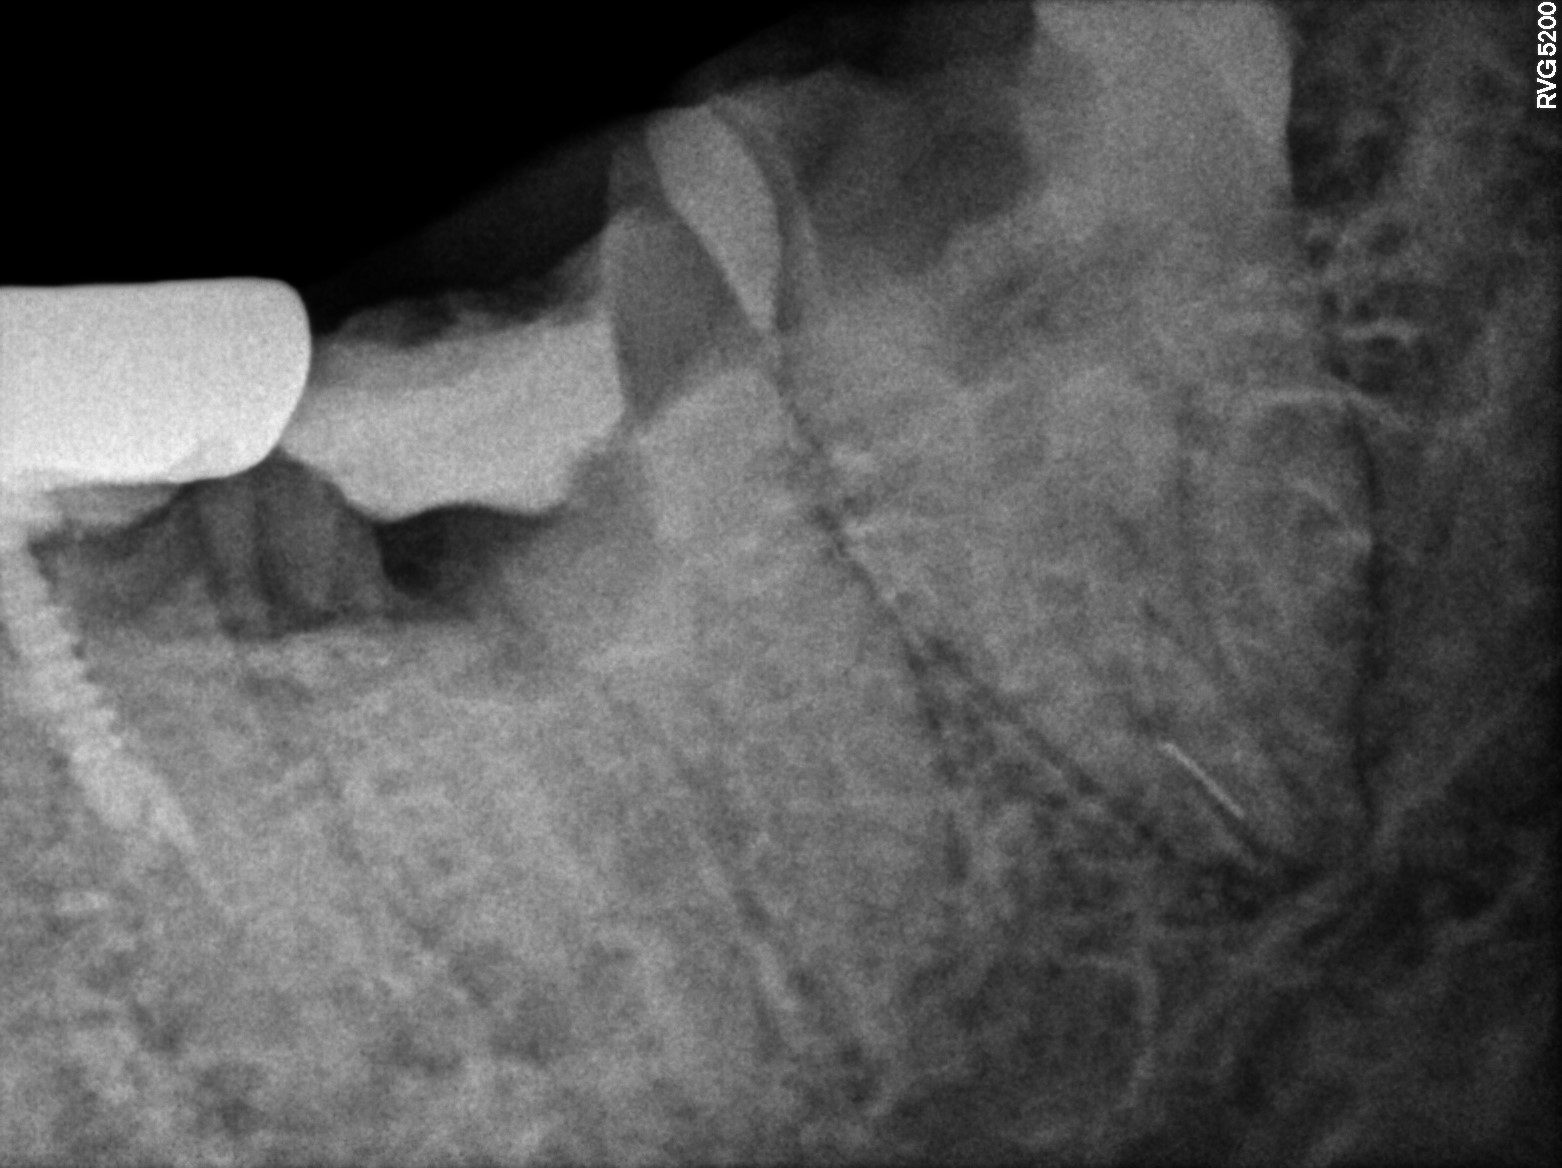

Dental Radiographs FHIR: DocumentReference · LOINC 24641-7

R56 (2).jpg

24641-7